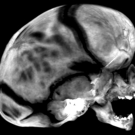

A 3-month-old boy was brought to the clinic by his mother with concern for abnormal head shape. He had been born at term via spontaneous vaginal delivery, without any complications.

05/27/2020